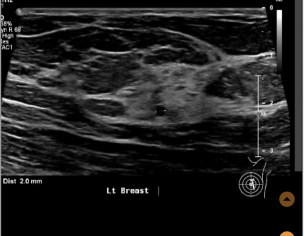

Left breast ultrasound report said no concerns. Symptoms - enlarged lymph nodes left breast, small cyst, changes in size and shape of left breast, dimples in lower left breast, pain in outer quadrant of left breast. Second opinion on ultrasound pics?